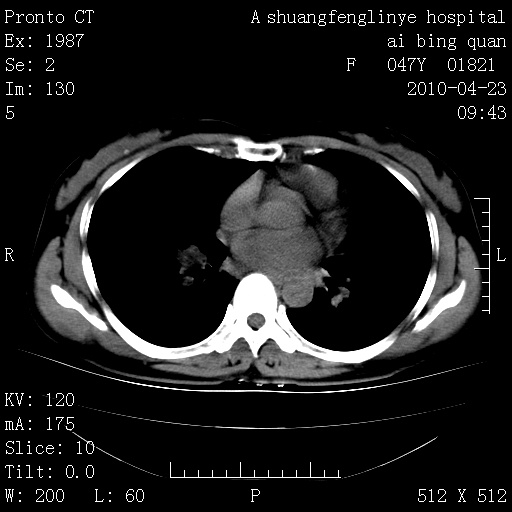

标题: CT25944:胸痛、气短、前几日高烧!肺Ca?请会诊! [打印本页]

标题: CT25944:胸痛、气短、前几日高烧!肺Ca?请会诊!

kaolv 周围型肺癌并同肺转移

双肺多发结节,考虑转移瘤,肺癌肺转移不除外

周围型肺癌并肺转移

双肺多发结节,部分密度较高,最大结节边缘光滑。临床有“胸痛、气短、前几日高烧”病史。首选考虑:右肺感染性病变!建议积极消炎后复查!